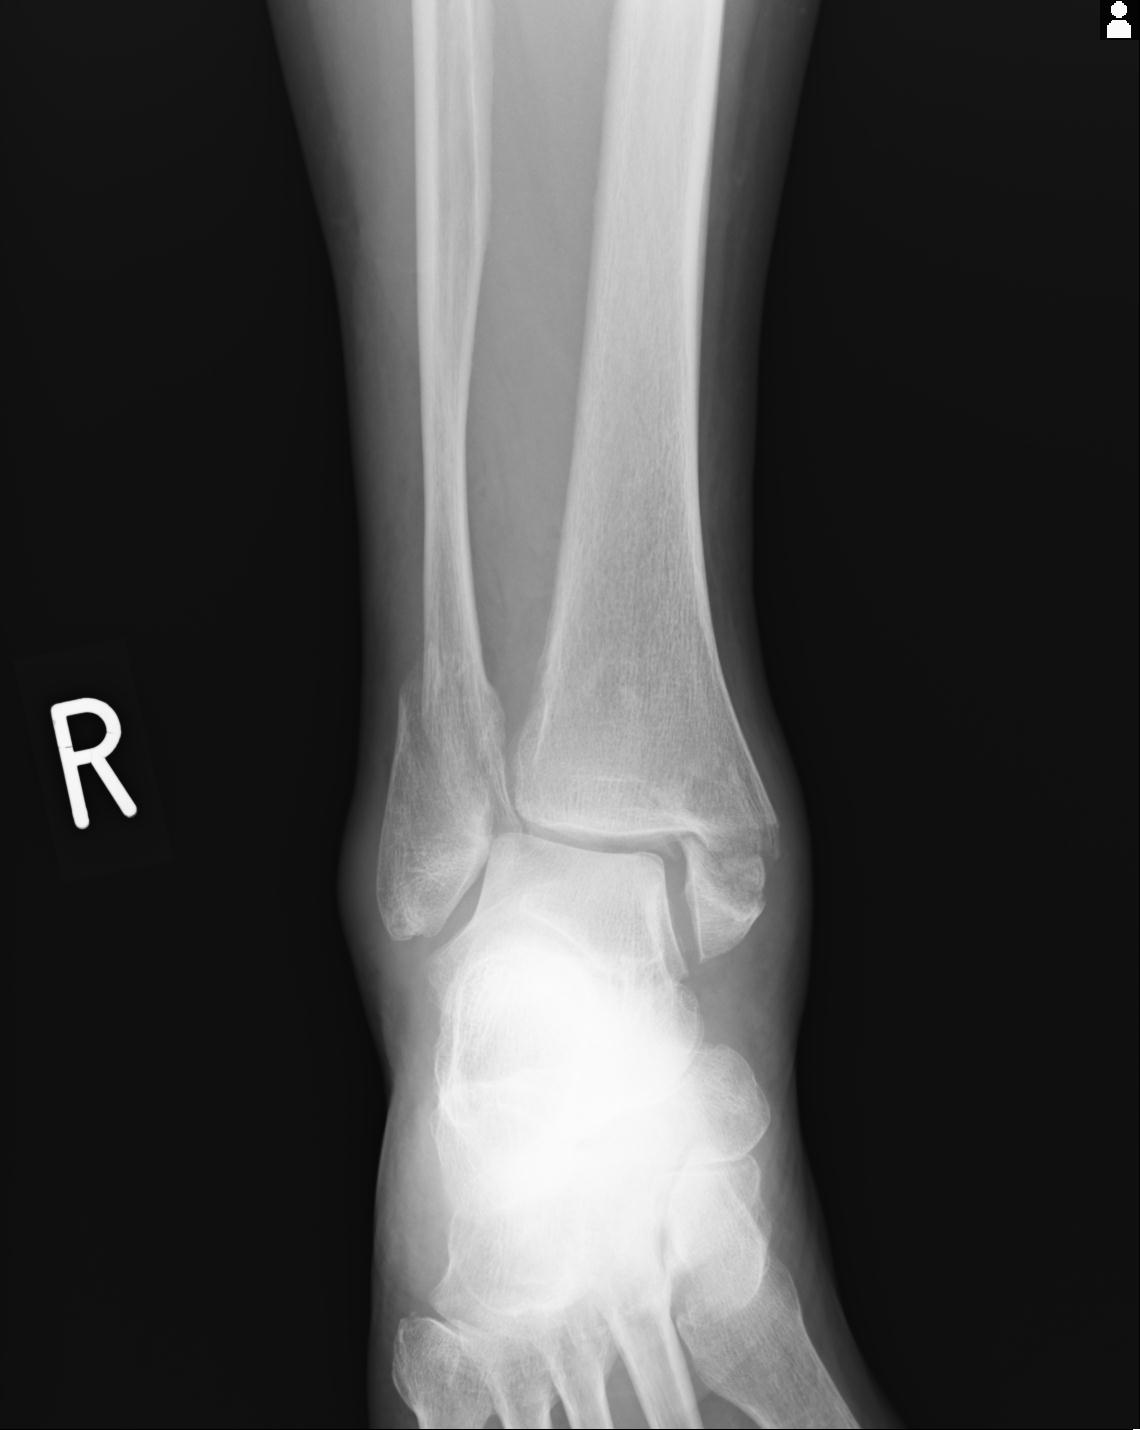

102755 1/4 2R 1/15 2R 右足関節 68歳女性 右三果脱臼骨折